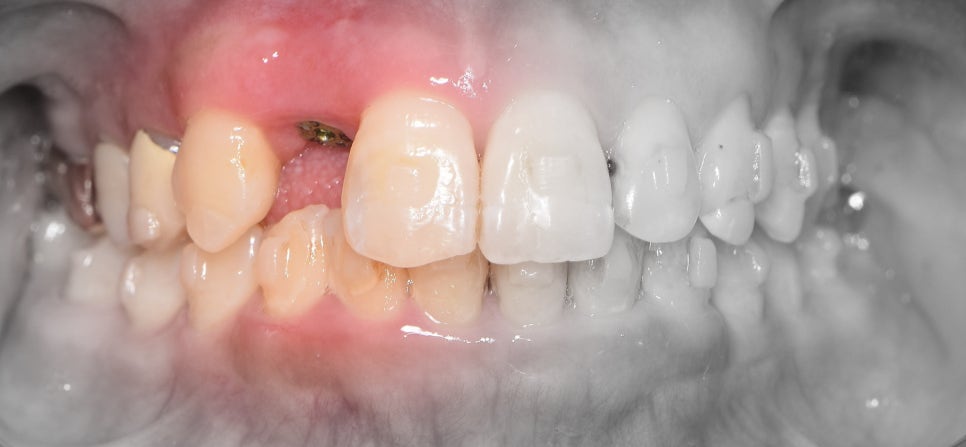

4. 발치와보존술 후, 고정체 식립 및

인비절라인 치아교정 치료 시작

- 치아의 총생 및 과개교합 이 원인

이제 최종 결과를 보여드리겠습니다.

이제, 흡잡을 곳이 없군요.

교정치료 및 발치와보존술, 임플란트 시술의

복합 결과를 보고 있으며 3년이라는 긴 기간이

소요되어서 원래의 구강 내 상태를 되찾아드렸네요.